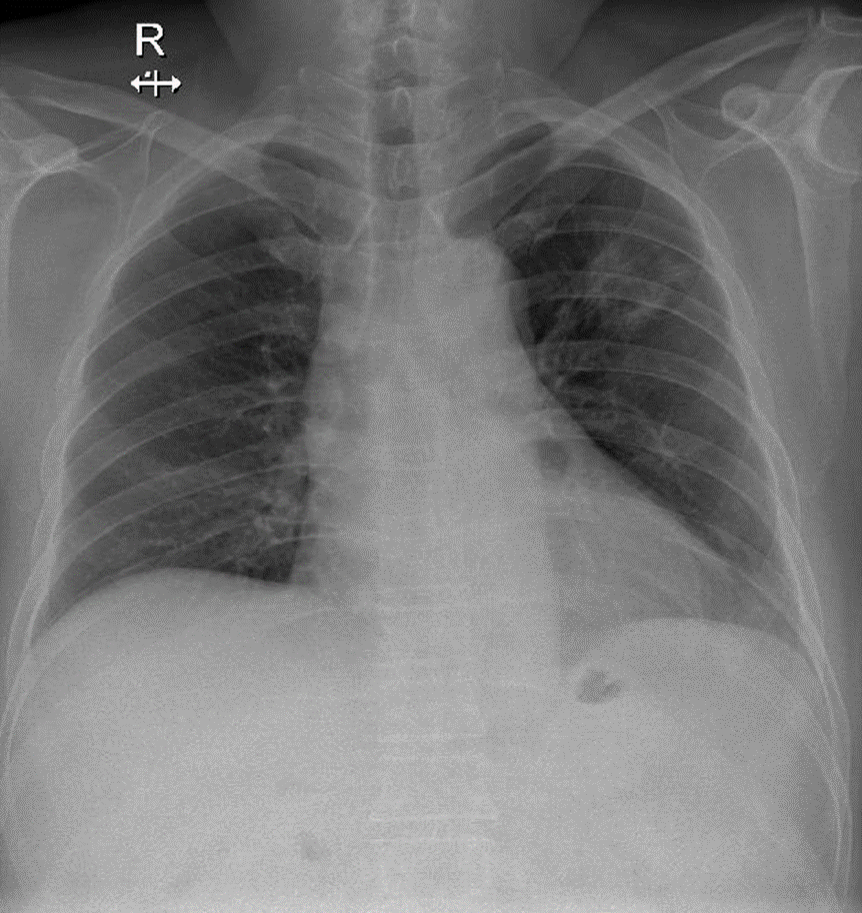

Hãy phân tích tình huống Nam

1-Hang lao thùy trên phổi (T)